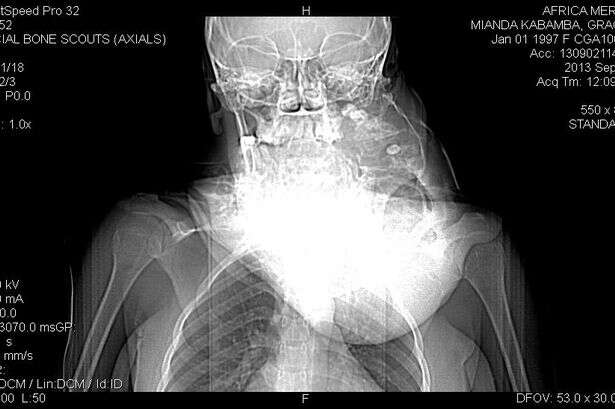

Uma adolescente com o rosto horrivelmente desfigurado por conta de um enorme tumor crescente em sua boca, passou por uma cirurgia para removê-lo.

Grace, de 17 anos, da República Democrática do Congo, estava convivendo com o tumor de crescimento contínuo há 10 anos.

Médicos de um hospital local não conseguiram ajudá-la, no entanto, um pastor cristão encontrou um lugar para ela ter uma operação para salvar sua vid, a bordo do Africa Mercy, do grupo Mercy Ships, uma organização não governamental (ONG) com bases cristãs, que possui um navio-hospital para prestar atendimento médico em diversos países do mundo.

Durante a operação de quatro horas, os médicos removeram o tumor, juntamente com vários dentes de Grace e sua mandíbula inferior, antes de colocar-lhe placas de titânio para substituir as partes retiradas de sua boca. INfo(verdinhoitabuna